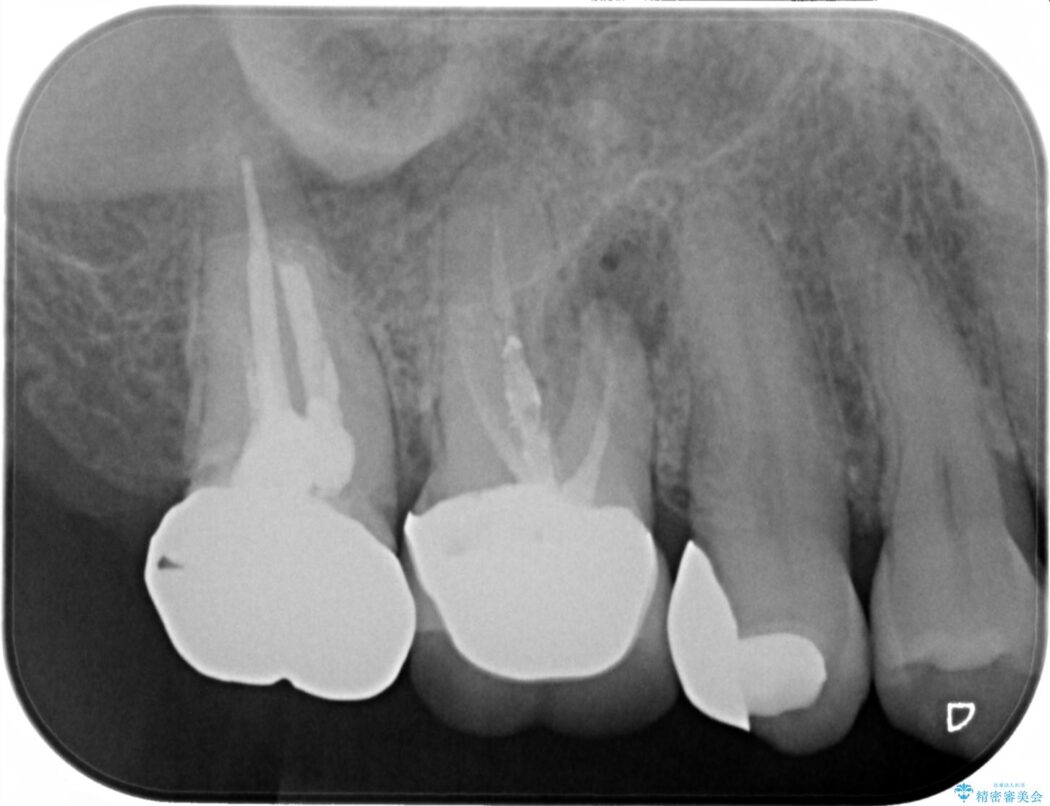

表面の見た目よりも骨の吸収が進行しており、抜歯と判断せざるを得ないような歯が多くありました。

予算的な制約があったため、右上のみインプラントにして、他はブリッジとする事で咬合を再構成しました。